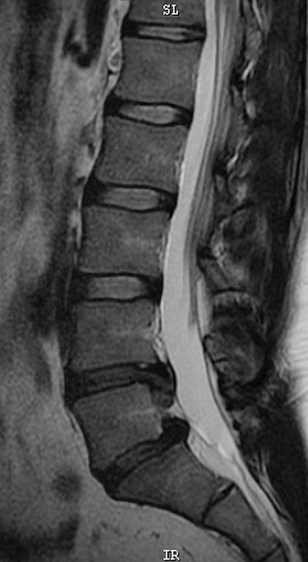

- Основным методом инструментальной диагностики при грыжах межпозвонковых дисков на современном этапе служит магнитно-резонансная томография позвоночника

Если по данным МРТ у пациента была выявлена грыжа межпозвонкового диска, то необходима обязательная консультация двух специалистов: невролога и нейрохирурга.